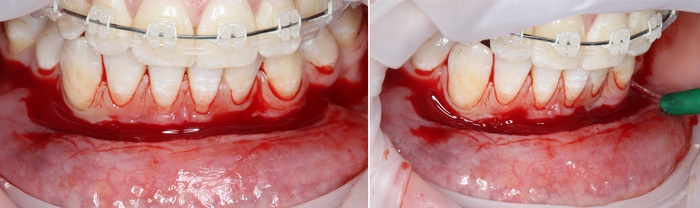

2 – проведение пластики десны.

Был взят трансплантат в области бугра верхней челюсти (это то место, где раньше был зуб мудрости).

Далее проведена пластика десны, снова два месяца ожиданий и установка временной коронки: